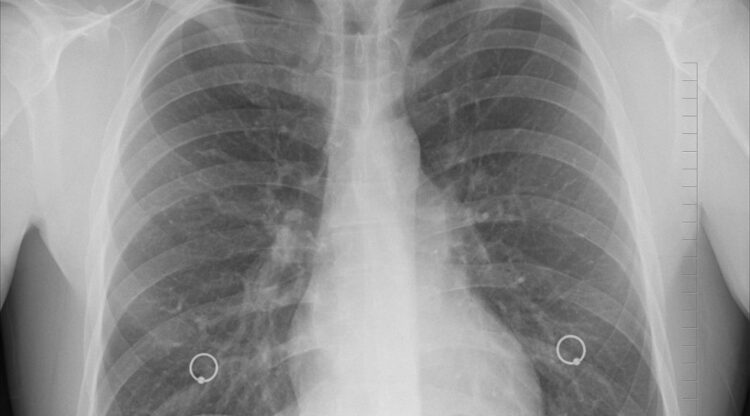

Il successo dei trattamenti è però legato alla precocità della diagnosi. Ed è per questo motivo che l’implementazione di un programma strutturato di screening polmonare deve rappresentare una priorità nell’ambito degli interventi e delle politiche di sanità pubblica.

“Parallelamente alla lotta al tabagismo- ha dichiarato la professoressa Giulia Veronesi, direttrice del Programma di Chirurgia Robotica Toracica presso l’Irccs ospedale San Raffaele- è prioritario favorire l’accesso allo screening ai soggetti ad alto rischio, cioè fumatori o ex forti fumatori sopra i 50 anni. Le società scientifiche internazionali e la Commissione europea stanno già andando in questa direzione e raccomandano, per questi soggetti, regolari TAC al torace a basso dosaggio di radiazioni intensità, per un monitoraggio adeguato”.

“Quando il tumore al polmone viene diagnosticato e trattato in fase precoce con chirurgia e farmaci- ha proseguito Veronesi- si possono raggiungere tassi di sopravvivenza a 5 anni intorno all’80%. Per questo, investire in un programma strutturato di screening polmonare è oggi più cruciale che mai, perché consente un guadagno di vita di oltre 7 anni a fronte di un risparmio economico per il Sistema sanitario nazionale”.